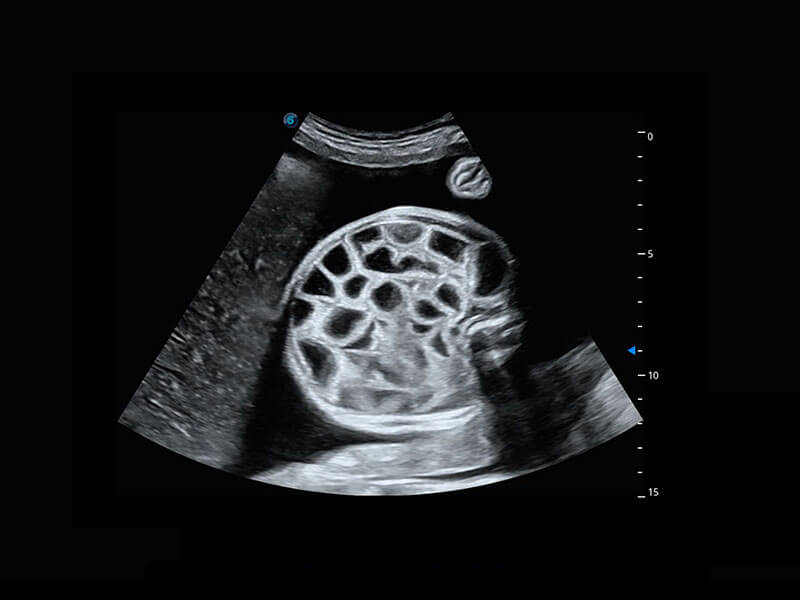

P60搭载一系列胎儿心脏成像技术,实现精细的胎儿心脏评估。

右室双出口